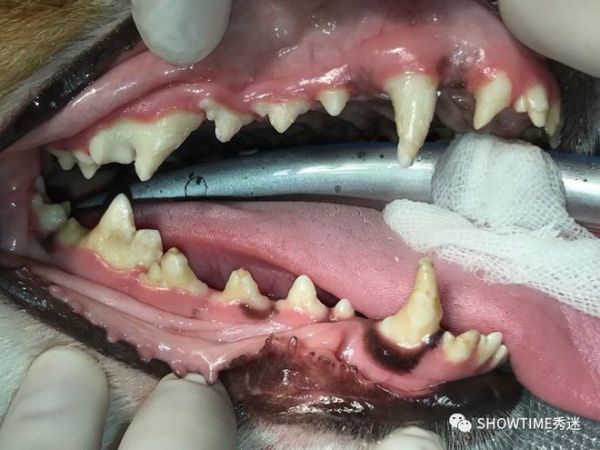

“Honey”是一只9个月大的柯基犬,它的家长发现“Honey”小小年纪牙齿上就有结石,看起来脏脏的,并且牙齿有明显的破损,不知道是怎么回事,就带它到医院来,看看要怎么办。

检查后发现“Honey”是很典型的牙齿珐琅质发育不全与钙化不全的情况,牙结石明显,而且出现破损,如果不进行修补治疗的话,可能导致严重的口腔问题。

“Honey”左侧还未处理前。

针对“Honey”的情况,我们跟它的家长讨论以后,决定替它进行牙本质小管的封闭,并且做全口牙科X-ray的检查。确保牙齿以后比较不容易感染。

治疗过程

左侧把牙结石与不健康牙组织去除后。